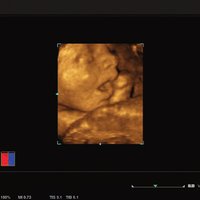

• Live 3D / 4D OBS/GYN

• HD Live

Das ACUSON NX2 Ultraschallsystem besitzt eine zukunftsfähige digitale Plattform mit nahezu unerreichter Bildqualität und sorgt für effiziente und zuverlässige Diagnosedaten. Die Vielseitigkeit des Ultraschallsystems wird mit einem großen kompatiblen Portfolio an Schallköpfen gedeckt, und so ist für jeden Anwendungsbereich etwas dabei. Die Bedienkonsole ist intuitiv aufgebaut und optimiert und erlaubt bis zu vier nach vorne gerichteten Schallkopfanschlüssen für eine enorme Effizienz und schnellen Workflow. So lassen sich bei der fetalen Bildgebung außergewöhnlich detailgetreue Darstellungen des Fetus im Gesicht zeigen oder durch die herausragende Farbdopplersensitivität bei der Darstellung der kleinen Gefäße des zystischen Schilddrüsenknotens kleinste Details erkennen. Weiterhin besticht das NX2 mit einfacher Aufrüstbarkeit bei wachsenden Anforderungen für Ihre zukünftigen Anwendungen und kompatible skalierbare Schallköpfe verringern ihren Kapitaleinsatz um bis zu 31 %.